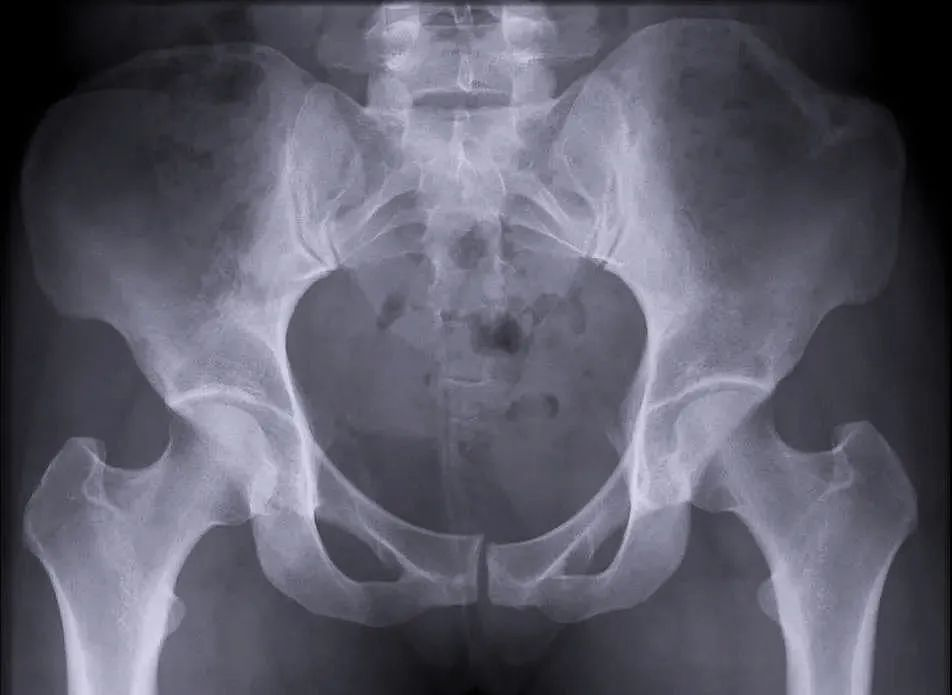

穩(wěn)定性骨折